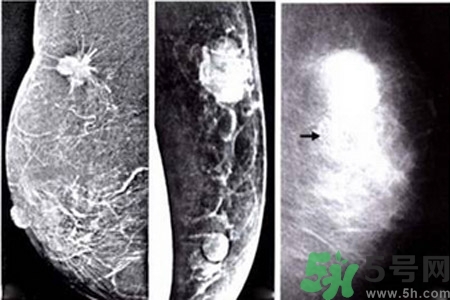

乳腺鈣化部位

了解鈣化部位應(yīng)強(qiáng)調(diào)多方位、多角度觀察。良性鈣化灶,多發(fā)生在纖維組織、脂肪、血管、大汗腺、皮膚等乳腺間質(zhì)內(nèi),乳腺實質(zhì)內(nèi)少見。惡性鈣化則多發(fā)生于乳腺實質(zhì)內(nèi),泥沙樣鈣化多發(fā)生在乳腺小葉腺泡內(nèi),小桿狀鈣化多發(fā)生在導(dǎo)管內(nèi),小叉狀鈣化則多位于末支小導(dǎo)管內(nèi)。

乳腺鈣化與腫塊的關(guān)系

鈣化可與腫塊并存,也可獨立存在;既可發(fā)生在病變內(nèi),也可獨立于腫塊之外。90%的導(dǎo)管原位癌是通過X線鉬靶照片發(fā)現(xiàn)的,且僅以乳腺內(nèi)鈣化作為惟一的表現(xiàn)形式。這是由于原位癌中央發(fā)生不規(guī)則壞死引起的鈣鹽在導(dǎo)管內(nèi)沉積或腫瘤細(xì)胞分泌而呈形態(tài)各異的的表現(xiàn)。